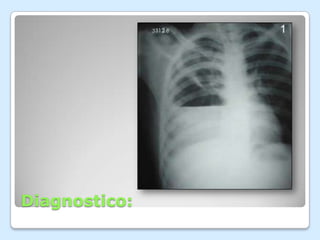

Diagnostico: Radiografía PA de tórax: de acuerdo con la intensidad del derrame así como el tiempo de evolución hay borramiento del seno costo diafragmático, borramiento de ambos senos, una sombra triangular de borde interno cóncavo, sombras atípicas a lo largo de las cisuras interlobares, densidad homogénea que ocupa parte o todo el hemitórax afectado y desplazamiento del mediastino hacia el lado opuesto.

Diagnostico: Radiografía PAde tórax: de acuerdo con la intensidad del derrame así como el tiempo de evolución hay borramiento del seno costo diafragmático, borramiento de ambos senos, una sombra triangular de borde interno cóncavo, sombras atípicas a lo largo de las cisuras interlobares, densidad homogénea que ocupa parte o todo el hemitórax afectado y desplazamiento del mediastino hacia el lado opuesto.